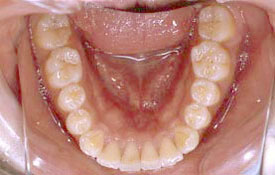

| プロフィール | 15歳 男性 |

| 所見 | アメリカから転院されて来られた方です。 インビザラインで上下顎の矯正治療を開始し下顎はアメリカで終了しており、上顎のみ治療の後期を担当しました。 アイライナーの装着は、1日平均22時間ほどでした。 |